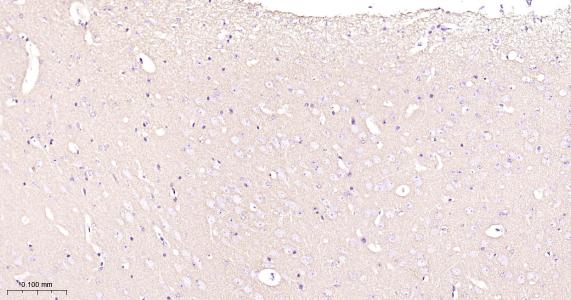

Paraformaldehyde-fixed, paraffin embedded Human Cerebrum; Antigen retrieval by boiling in sodium citrate buffer (pH6.0) for 15 min; Antibody incubation with Hexokinase 1 Monoclonal Antibody, Unconjugated (bsm-61212R) at 1:200 overnight at 4°C, followed by conjugation to the bs-0295G-HRP and DAB (C-0010) staining.

Paraformaldehyde-fixed, paraffin embedded Rat Cerebrum; Antigen retrieval by boiling in sodium citrate buffer (pH6.0) for 15 min; Antibody incubation with Hexokinase 1 Monoclonal Antibody, Unconjugated (bsm-61212R) at 1:200 overnight at 4°C, followed by conjugation to the bs-0295G-HRP and DAB (C-0010) staining.

Paraformaldehyde-fixed, paraffin embedded Mouse Cerebrum; Antigen retrieval by boiling in sodium citrate buffer (pH6.0) for 15 min; Antibody incubation with Hexokinase 1 Monoclonal Antibody, Unconjugated (bsm-61212R) at 1:200 overnight at 4°C, followed by conjugation to the bs-0295G-HRP and DAB (C-0010) staining.